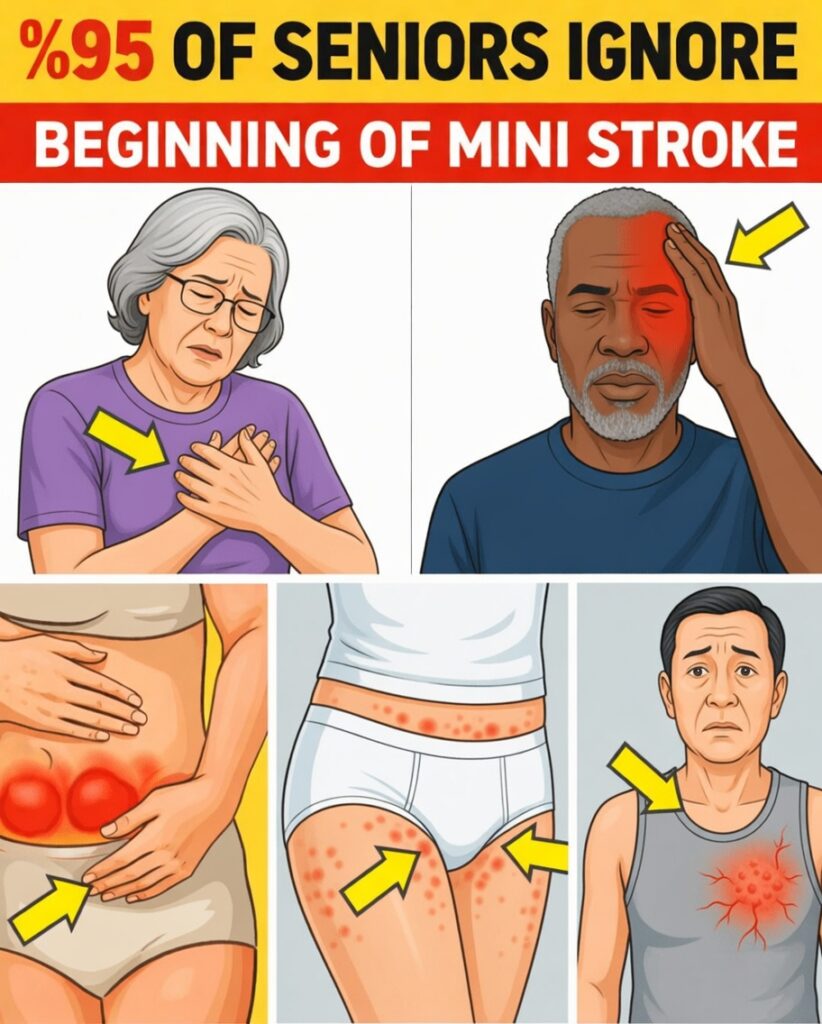

Silent Mini Stroke Symptoms After 60: 10 Signs You Should Never Ignore

Many people over 60 notice odd, short-lived sensations during everyday life—a heavy arm while sipping morning coffee, sudden unsteadiness while walking, or a brief spell of blurry vision that disappears within minutes. These episodes are often dismissed as “just getting older,” yet they can quietly fuel stress about losing independence and worry loved ones who sense something is wrong.

In some cases, these fleeting changes are not simply age-related. They may be silent mini stroke symptoms, subtle warning signs that the brain is not getting enough blood for a short period of time. Because these symptoms come and go so quickly, they are easy to overlook—yet they can signal a higher risk of a future, more serious stroke.

Recognizing silent mini stroke symptoms early gives you the chance to seek medical evaluation promptly and protect your long-term health. Below are 10 commonly missed signs, including the especially surprising symptom at #4 that many people never connect with a mini stroke.

Silent mini stroke symptoms can be subtle, brief, and easy to brush off as normal aging. If you are over 60, pay close attention to the following 10 signs. Any of these symptoms—especially if they start suddenly, affect only one side of the body, or are new for you—deserve prompt medical attention.

5. Numbness or Tingling That Comes and Goes on One Side

A sudden sensation of pins and needles, numbness, or loss of feeling in your face, arm, or leg—typically on one side of the body—is a classic silent mini stroke symptom. It may last only a few minutes and then vanish, making it easy to dismiss.

1. Sudden Weakness in One Arm or Leg

The most critical and well-known silent mini stroke symptom is sudden weakness or heaviness in one arm, one leg, or both on the same side. You might notice:

- Difficulty lifting an arm or holding an object

- A leg that feels heavy, making it hard to walk or climb stairs

- A sensation that one side of your body is not responding normally

2. Brief Facial Droop or Asymmetry

You glance in the mirror or talk with someone, and for a moment one side of your face looks different—perhaps your mouth droops slightly or your smile is uneven. Then everything appears normal again.